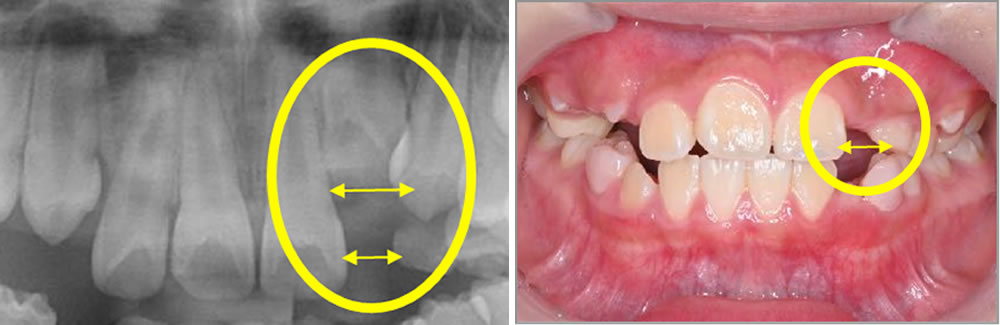

こちらの患者さまは、当院の一般歯科の初診で「上の前から2番目の歯で、乳歯が抜けた後になかなか永久歯が生えてこない」との主訴で来院されました。

お口を拝見すると、上顎左側側切歯が萌出していない状態でした。反対側の右側側切歯はしっかりと萌出しており、本来であれば萌出していなければならない時期でした。

- 上顎左側側切歯の萌出遅延:スペースが不足し、生えてくる場所がなく歯が出てこない状態

生えてくる場所がない:歯がキツキツで生えてこられない